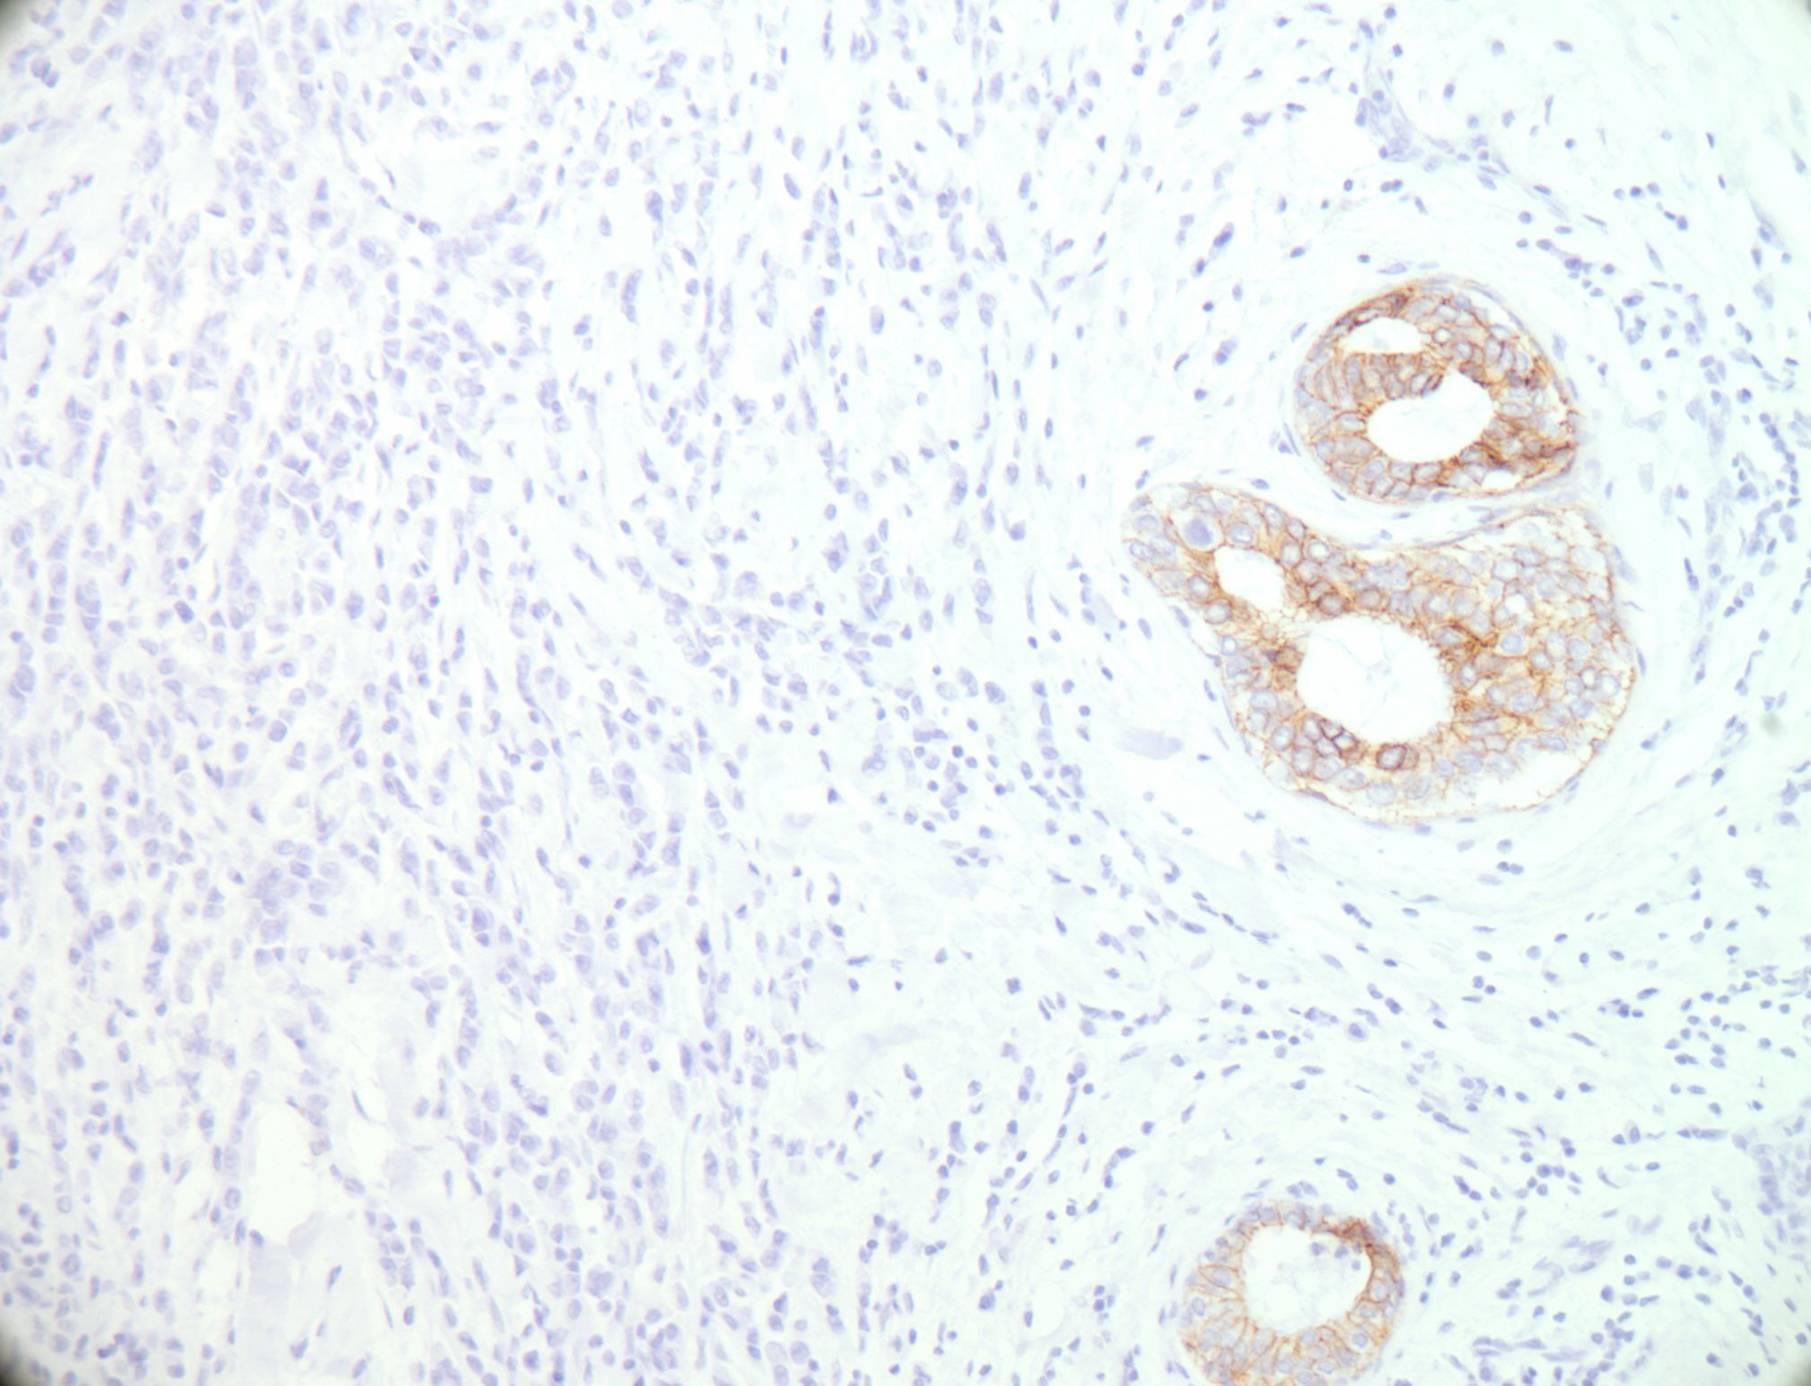

Pure tubular carcinomas ± 5% of all invasive breast carcinomas Bland tubules with angulated outline and open lumen Haphazard tubular arrangement in a desmoplastic stroma SMM and p63 negative Good prognosis compared to other invasive ductal carcinoma

ΔΔ Sclerosing adenosis

Tubular ca SMM

A 43 year old female has a mammographically detected stellate lesion with dense central fibrosis. Histology shows central fibrosis and elastosis from which ducts radiate out. The ducts are positive for p63 and SMM.

Central fibroelastosis Entrapped benign ducts Associated epithelial hyperplasia <1cm radial scar >1cm complex sclerosing lesion Increased risk for subsequent breast cancer development

ΔΔ Tubular carcinoma (myoepithelial markers are helpful)